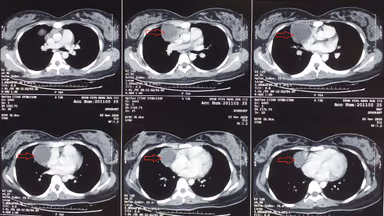

– Chụp cắt lớp vi tính (CT scan) vùng trung thất.